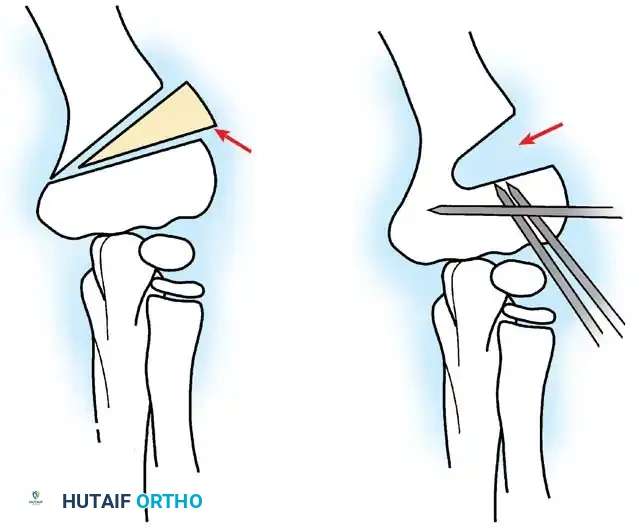

Fig. 33-42 Reduction technique for radial neck fractures.

- Positioning: The patient is placed supine. An assistant firmly stabilizes the distal humerus and the radius distal to the fracture site.

- Maneuver: With the elbow in full extension, the surgeon applies a strong varus stress to the elbow with one hand. This opens the radiocapitellar joint laterally.

- Reduction: Using the thumb of the opposite hand, direct lateral-to-medial pressure is applied over the tilted radial head to lever it back into anatomical alignment.

- Immobilization: The forearm is then placed in 90 degrees of flexion and pronation to lock the reduction.

Fig. 33-45 Mechanism of reduction of radial neck fracture.